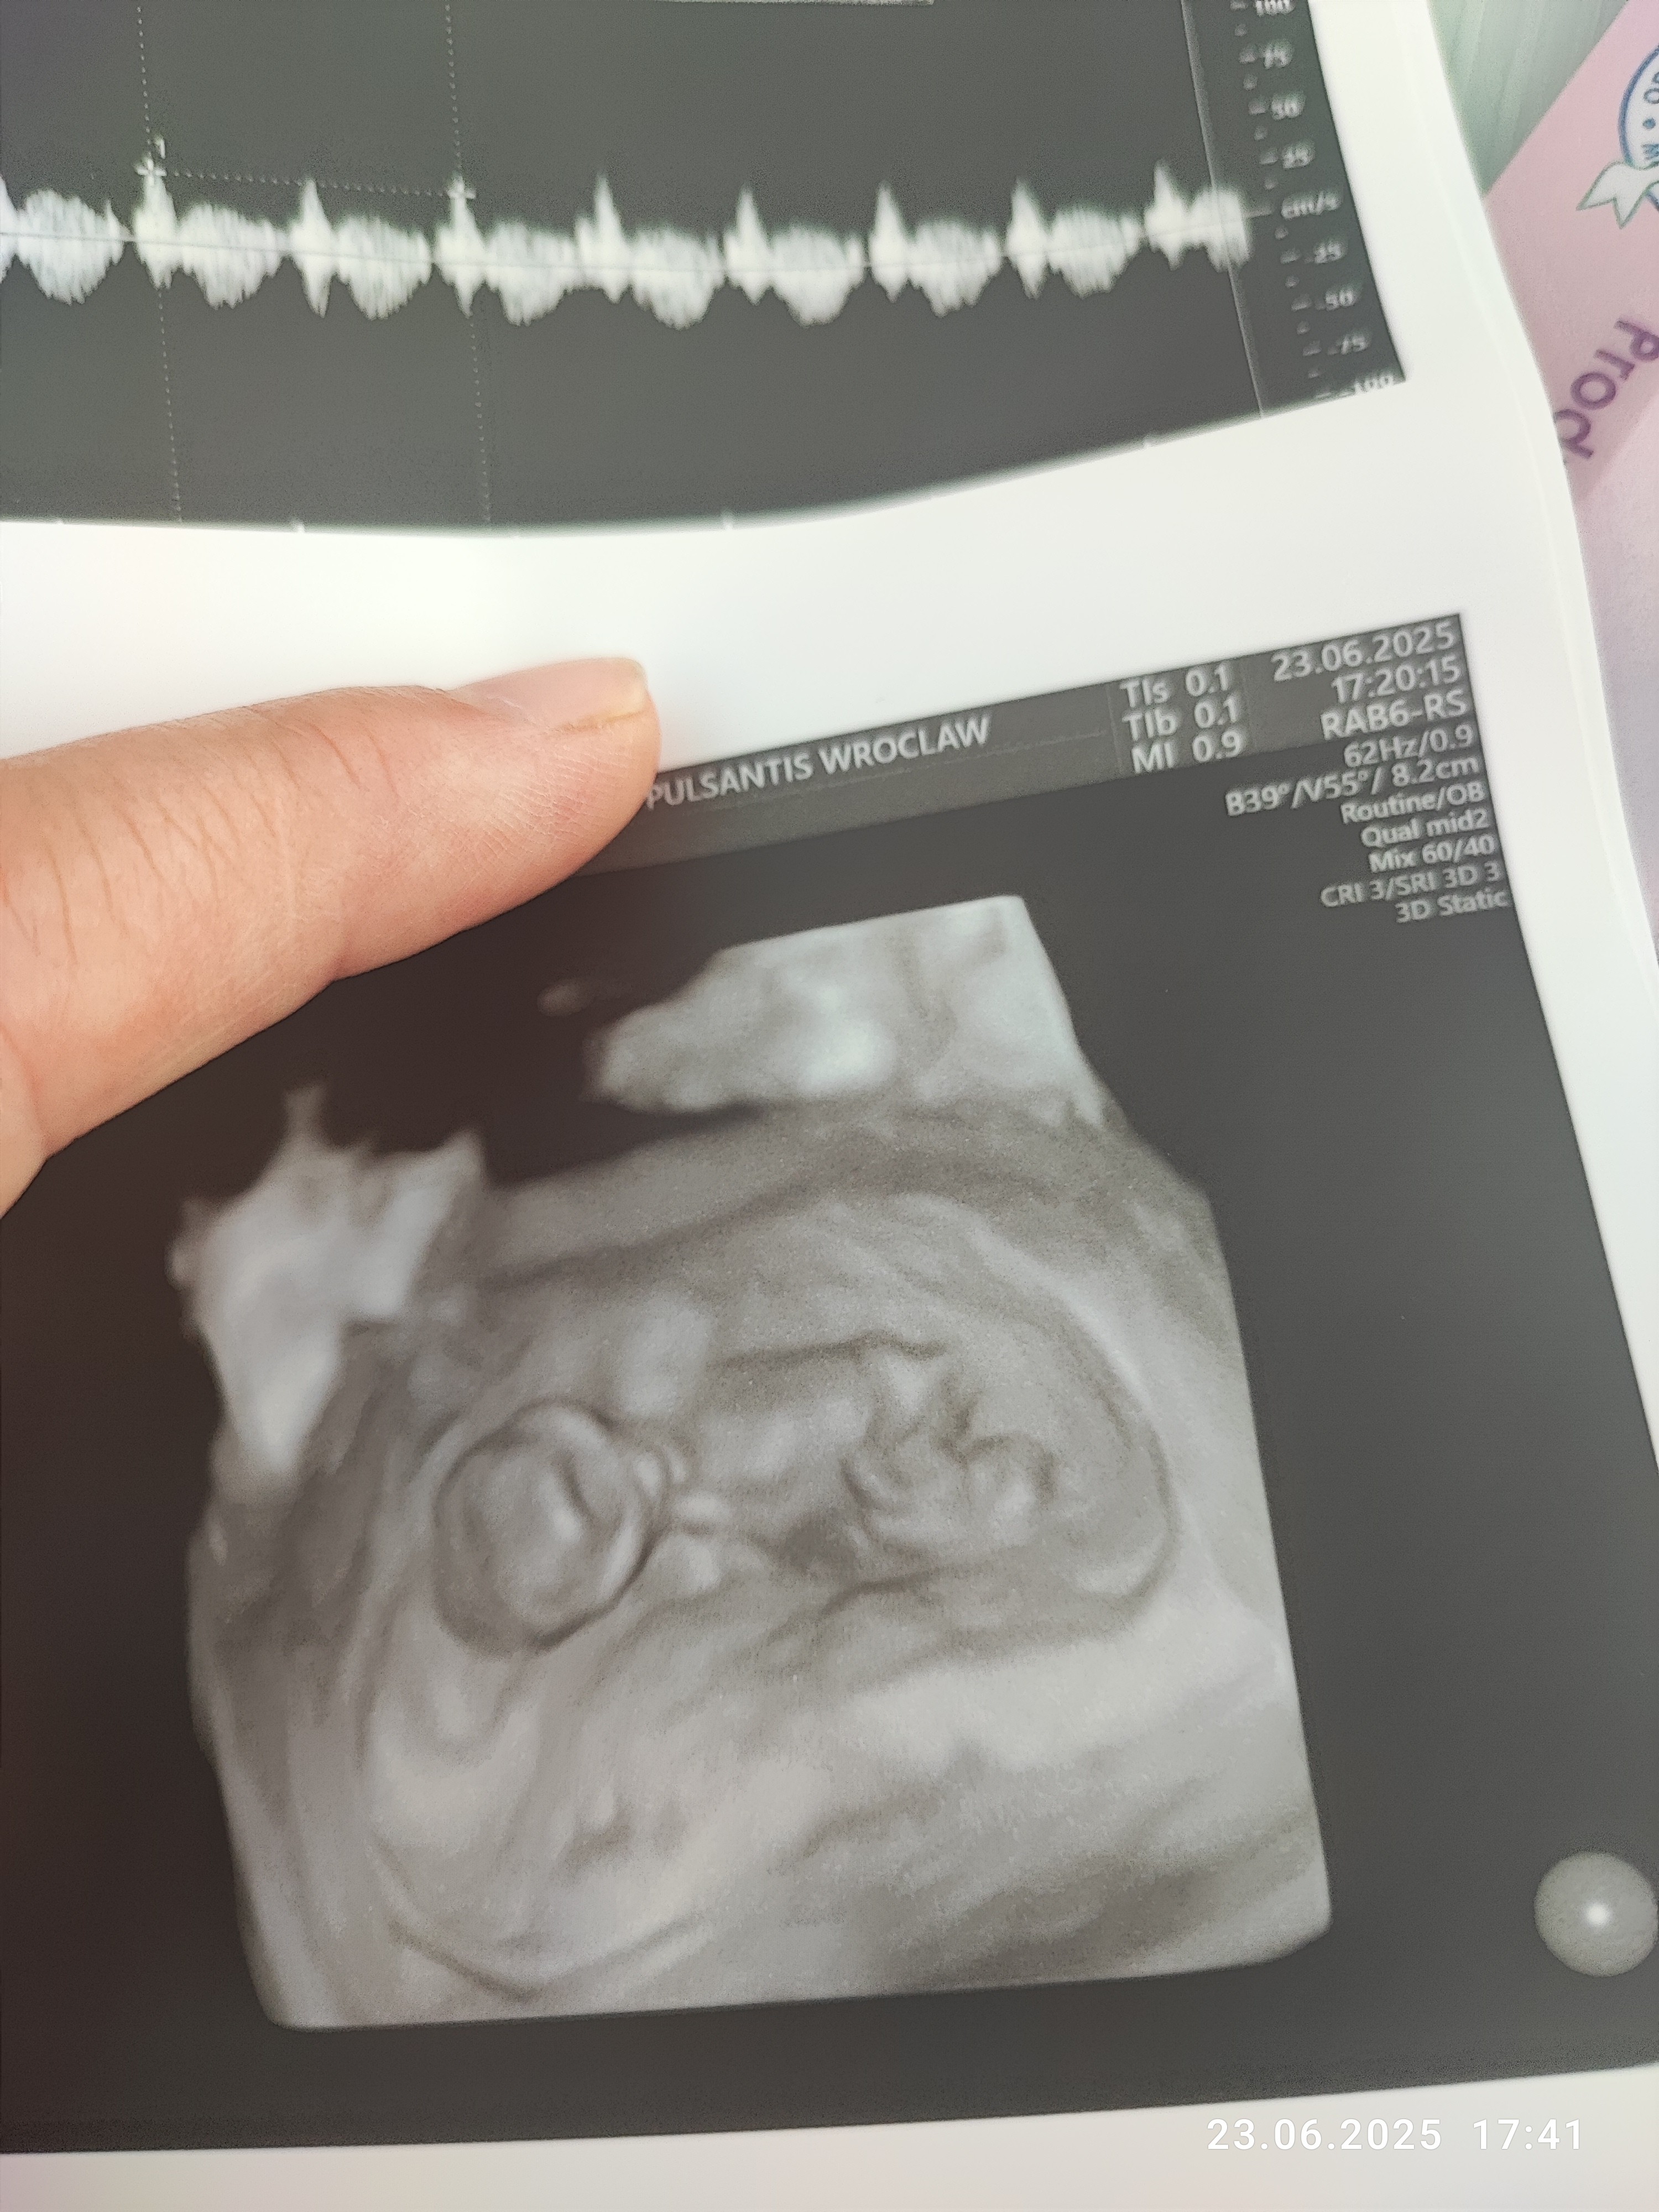

Cudowne wieści, gratulacje @SzklanaKulka i @anusia87, piękne dzidziusieTo i ja swojego bejbuna pokaże! A co![]()